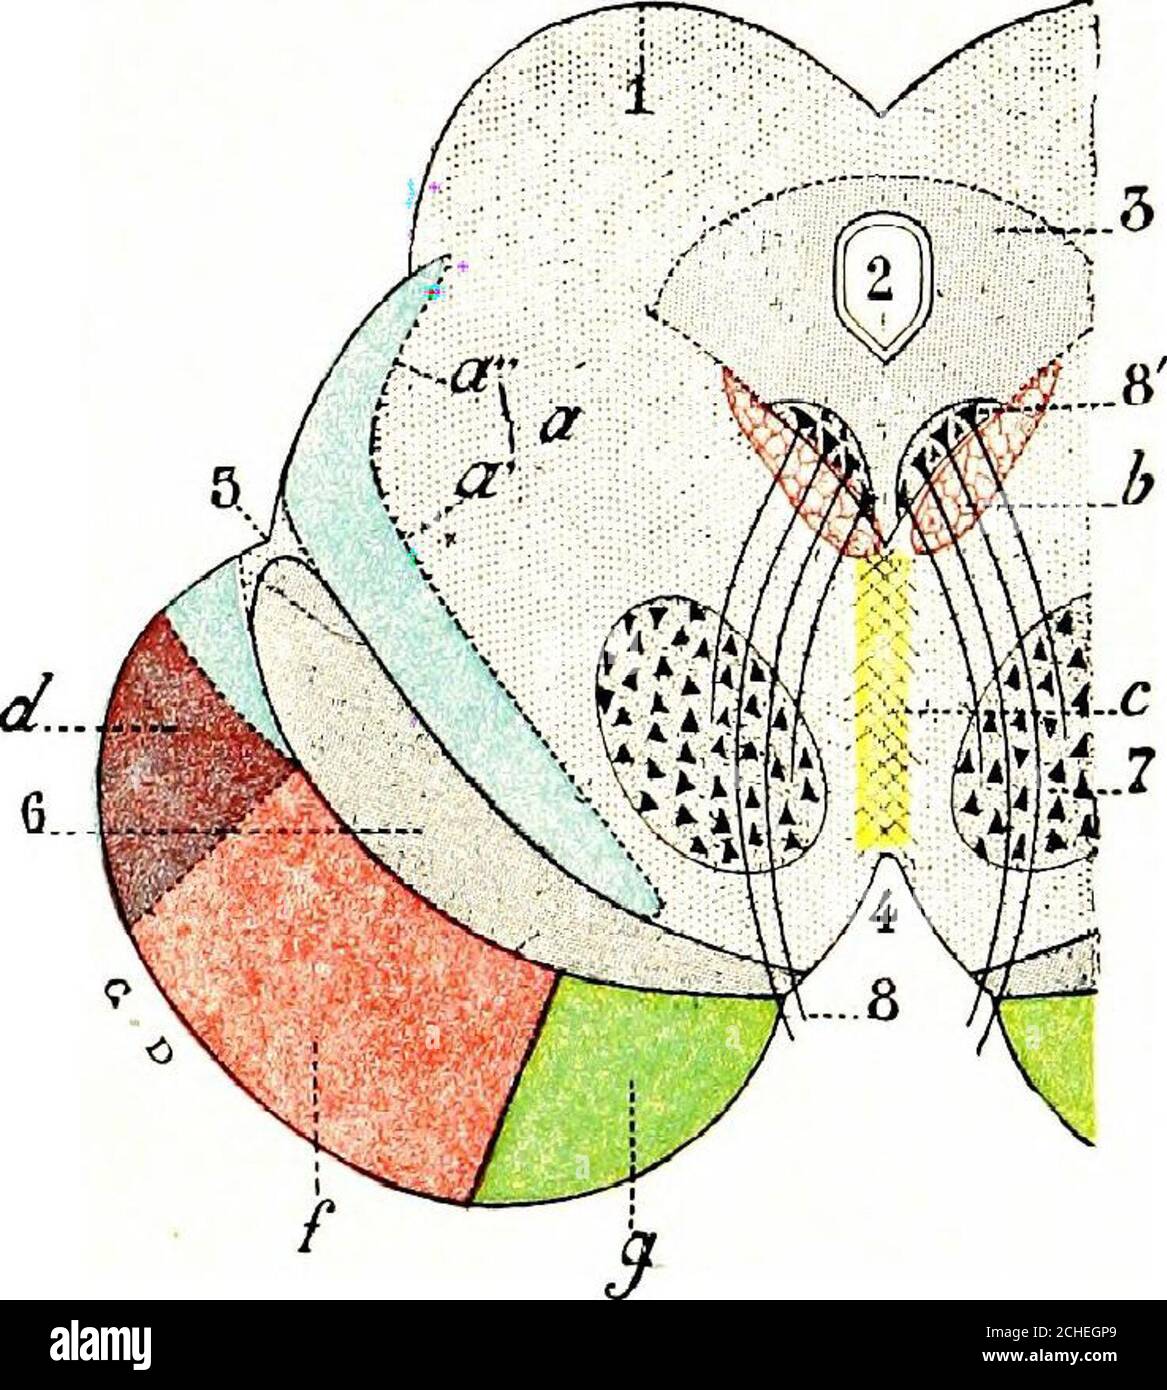

RM2CHEGP9–. Das Nervensystem: Ein elementares Handbuch der Anatomie und Physiologie des Nervensystems für den Einsatz von Studenten der Psychologie und Neurologie. Diese Nut der dritten Hirnnerven entstehen. Wo die Krura an die Ponen anschließt, liegen sie nahe beieinander, aber wenn sie vorwärts gehen, divergieren sie, so dass ein dreieckiger interpedukulärer Raum. Innere Struktur. - in einem transversem Abschnitt über die Mitte des Gehirns kann das Aquädukt von Sylvius in der Nähe der überlegenen Oberfläche (Abb. L 56, S. Graue Materie. - die wichtigen Massen der grauen Materie dieser Region vielleicht in vier Gruppen angeordnet : (1) die graue Materie surroun

RMPFYB74–. Cunninghams Lehrbuch der Anatomie. Anatomie. PAETS abgeleitet aus dem ZWISCHENHIRN. 617 davon, welche das Aquädukt umgibt, ist direkt kontinuierlich mit der grauen Substanz der substantia perforata posterior und Tuber cinereum, und auf diese Weise kommt es zu der Oberfläche in der Unterseite des Gehirns. Die optic Chiasma kreuzen den Boden vor und markiert die Stelle, wo der Letzteren stetig mit der anterioren Wand des Hohlraums wird. Die vordere Wand des dritten Ventrikels wird durch die Lamina terruinalis, die sich nach oben erstreckt sich von der Optic chiasma gebildet. Die anteriore com-missure, wie es kreuzt von einem

RM2AN4TWY–Handbuch der allgemeinen, beschreibenden und pathologische Anatomie (Band 2). Ventrikel, ein. Ventrikel des Kleinhirns, b. Aquädukt von Sylvius, C. Dritten Ventrikel, d. Lateralen Ventrikel, 1. Vordere Horn, 2. Hintere Horn, 3. Absteigend Horn, II. Textur, III. Gewicht, IV. Konsistenz, Kap. Iii. Umhüllt des Gehirns. Abt. Ich. Pia - mater, I. des Rückenmarks, II. Von Hirn, ein. - Externe Pia mater, b. Interne pia-mater, ich. Choroid Plexus des vierten Ventrikel, ii. Choroid Plexus des Großhirns, Art.ii.Apert-syndrom Membran, Art. hi. Dura-mater, I. spinalen Dura-mater, II. Zerebrale Dura-mater